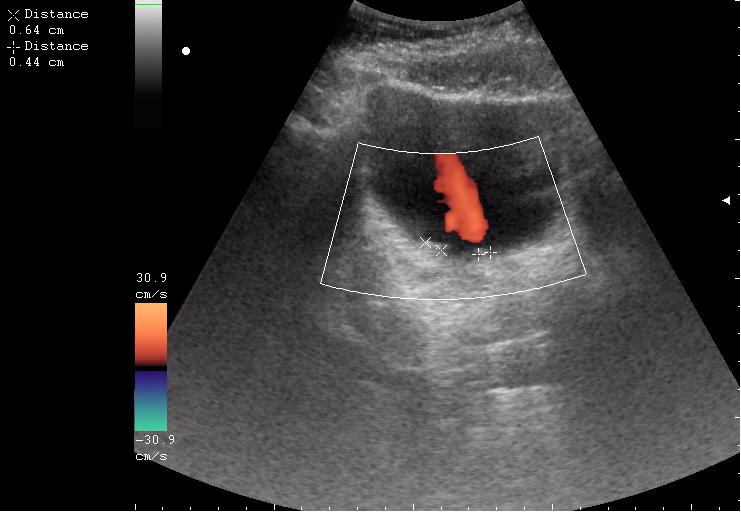

Сравните

Продольное сканирование мочевого пузыря После легкой перкуссии мочевого пузыря

Богу богово, кесарю - кесарево (я про анализы и клинические данные). На сонограммах неубедительно продемонстрирован осадок да и стенки м.п. не утолщены.

зато какое наполнение! а осадок убедительный! а же не 7-кой смотрела!На сонограммах неубедительно продемонстрирован осадок да и стенки м.п. не утолщены.